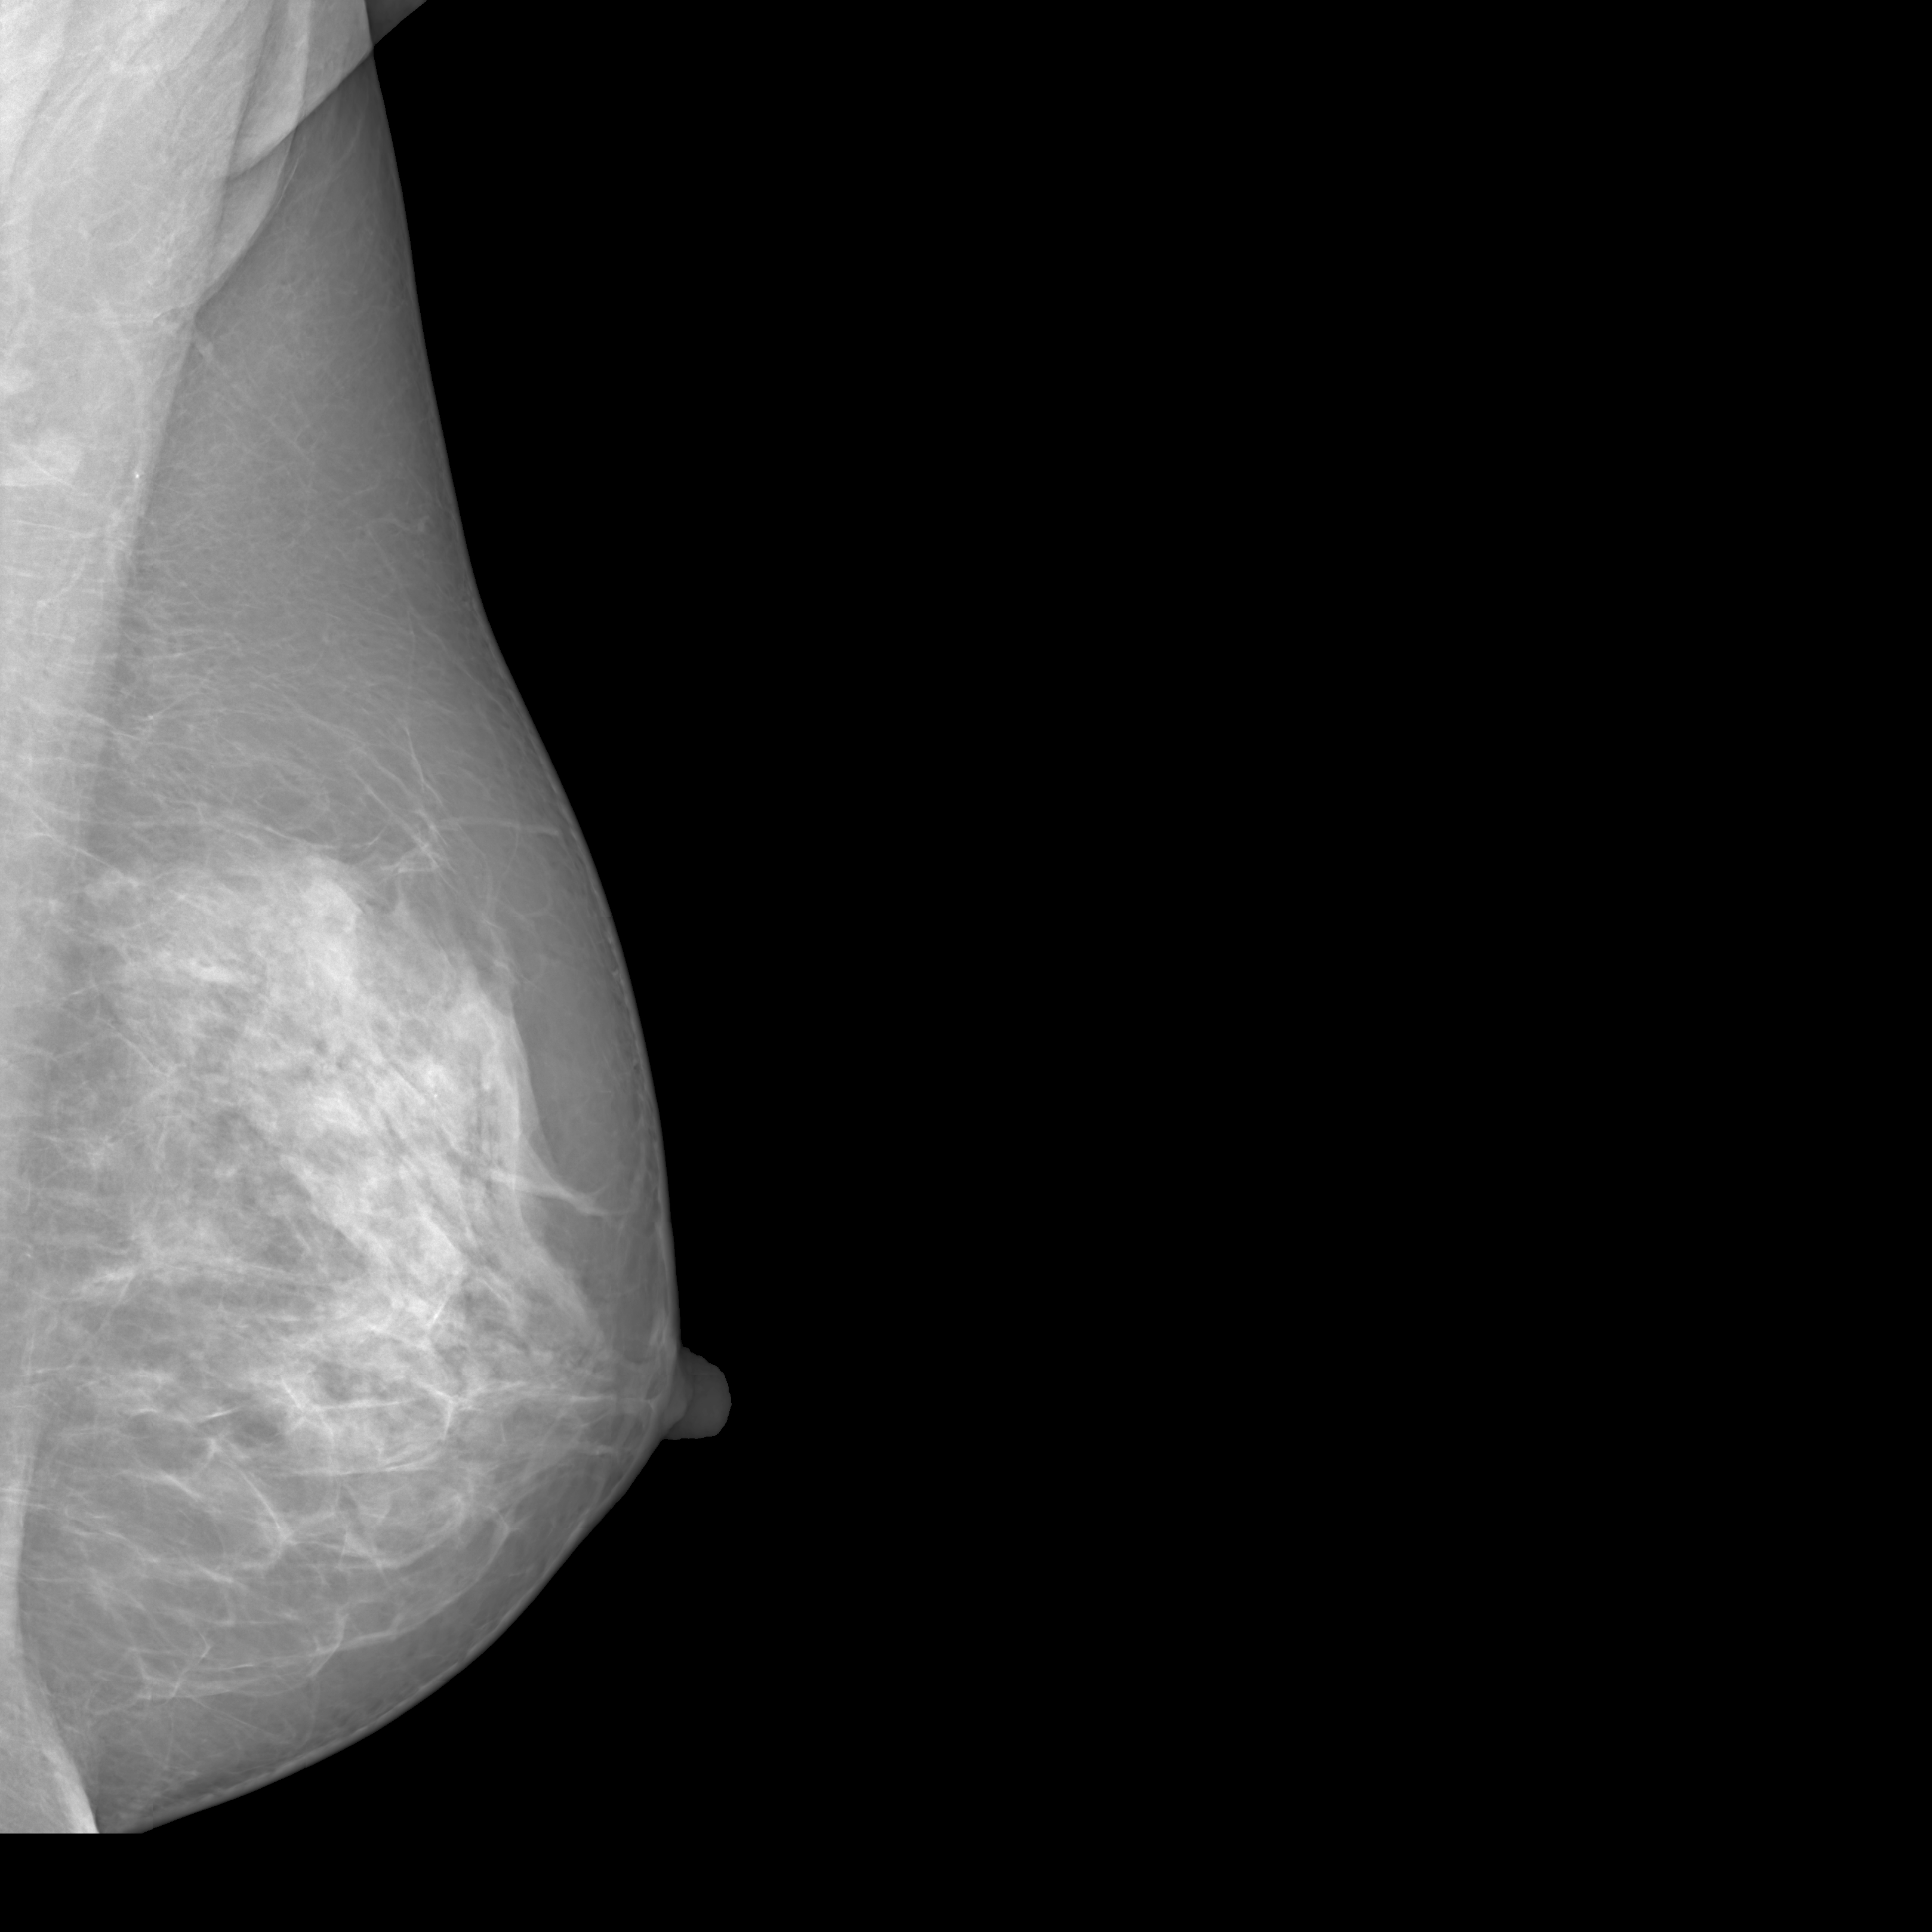

To overcome these challenges, this paper introduces MAMmography ensemBle mOdel (MAMBO), a novel approach that leverages an ensemble of diffusion models to generate mammography images at their native resolution. MAMBO uses a patch-based approach for generation which is conditioned both on local and global (full-image) context. In a nutshell, MAMBO involves the development of three distinct models: the first generates “standard”-resolution ( pixels) images to provide global context; the second increases the resolution to create local context for the target patch; and the third combines the outputs of both models to guide the generation of high-resolution patches, which are then reconstructed into a full-resolution synthetic mammogram. An example of a synthetic image generated by MAMBO is shown in Fig. 1. The image presents details at multiple resolutions, corresponding to the global and local contexts, and individual patch at full resolution. To the best of our knowledge, this is the first work to propose a diffusion model approach for generating very high-resolution synthetic mammograms.

What MAMBO can achieve in terms of qualitative results is presented in Fig. 1 and Fig. 3(d). MAMBO is able to generate high-quality images that are visually indistinguishable from the originals, representing plausible mammogram data to layman eyes. Results are also validated with expert radiologists, with quantitative results shown in Sec. 4.2.

Fig. 3(d) illustrates what MAMBO can achieve in terms of whole mammogram generation. When using global and local context data extracted from an original image, the denoised image (Fig. 3(b)) is difficult to distinguish from the original (shown in Fig. 3(a)). When providing only the original global context and generating local context and target patches from noise, we still observe good results, as we show in Fig. 3(d).

The mammograms generated using MAMBO (all three models connected in a pipeline) are shown on Fig. 13 and Fig. 14. The model is designed to generate full-square images to accommodate varying breast proportions. However, the provided examples are cropped to focus solely on the breast region.